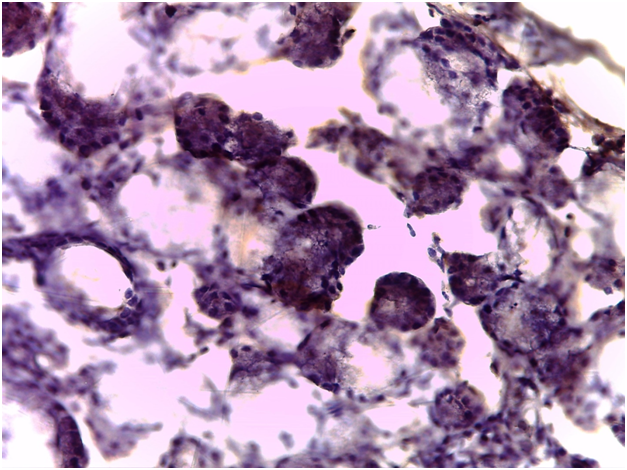

For Sjögren’s syndrome, salivary gland biopsy specimens have shown numerous lymphocytic foci in 4 mm2 (count > 50 lymphocytes per focus) within the glandular parenchyma. Acinar degeneration and few epimyoepithelial islands were detected. There was no substantial confluence of lymphocytes in a germinal-center-orientation within the submitted cases (Figure 3 & Figure 4). Focusing on characterizing any histopathological changes in GBS, the submitted cases of GBS revealed, in the asymptomatic glandular specimens, conspicuous perivascular and periductal infiltrations of neutrophils and macrophages. Moreover, vascularity was richer than that of normal mucosa whose vascular components were inconspicuous. Hemorrhagic spots, intervening extravasation of RBCs as well as dark acini, comparable to dust cells in smoking alveolitis, were also evident (Figure 5 & Figure 6).

Figure 5 photomicrograph showing hemorrhage and vascular rupture along with darker dusty acini and periductal inflammatory infiltrates (H&E stained, Original magnification 10x)..

Figure 6 Photomicrograph showing hemorrhage and macrophage-laden acini “dusty acini” (H&E stained, Original magnification 40x).